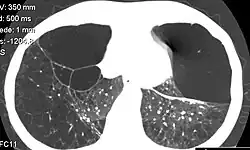

Individuals with A1AD may develop emphysema,[1] or chronic obstructive pulmonary disease during their thirties or forties even without a history of smoking, though smoking greatly increases the risk.[7] Symptoms may include shortness of breath (on exertion and later at rest), wheezing, and sputum production. Symptoms may resemble recurrent respiratory infections or asthma.[8]

A1AT is a glycoprotein mainly produced in the liver by hepatocytes,[9] and, in some quantity, by enterocytes, monocytes, and macrophages.[12] In a healthy lung, it functions as an inhibitor against neutrophil elastase,[13] a neutral serine protease that controls lung elastolytic activity which stimulates mucus secretion and CXCL8 release from epithelial cells that perpetuate the inflammatory state.[14] With A1AT deficiency, neutrophil elastase can disrupt elastin and components of the alveolar wall of the lung that may lead to emphysema, and hypersecretion of mucus that can develop into chronic bronchitis.[15] Both conditions are the makeup of chronic obstructive pulmonary disease (COPD).[16]

Normal blood levels of alpha-1 antitrypsin may vary with analytical method but are typically around 1.0-2.7 g/L.[17] In individuals with PiSS, PiMZ and PiSZ genotypes, blood levels of A1AT are reduced to between 40% and 60% of normal levels; this is usually sufficient to protect the lungs from the effects of elastase in people who do not smoke. However, in individuals with the PiZZ genotype, A1AT levels are less than 15% of normal, and they are likely to develop panlobular emphysema at a young age. Cigarette smoke is especially harmful to individuals with A1AD.[7] In addition to increasing the inflammatory reaction in the airways, cigarette smoke directly inactivates alpha-1 antitrypsin by oxidizing essential methionine residues to sulfoxide forms, decreasing the enzyme activity by a factor of 2,000.